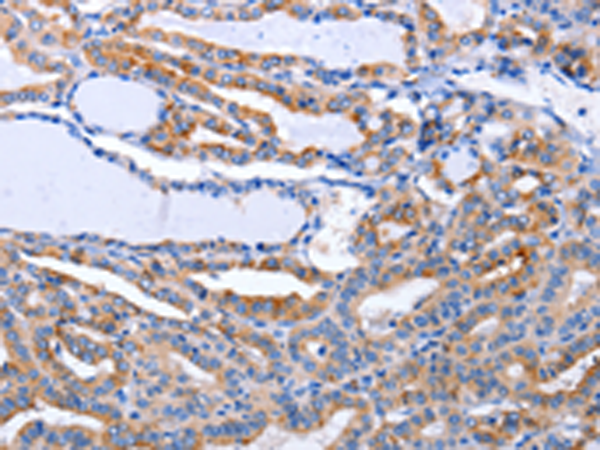

分类: 科研抗体货号: P10998别名: CDF, DIA, HILDA, MLPLI应用: IHC反应种属: Human, Mouse, Rat